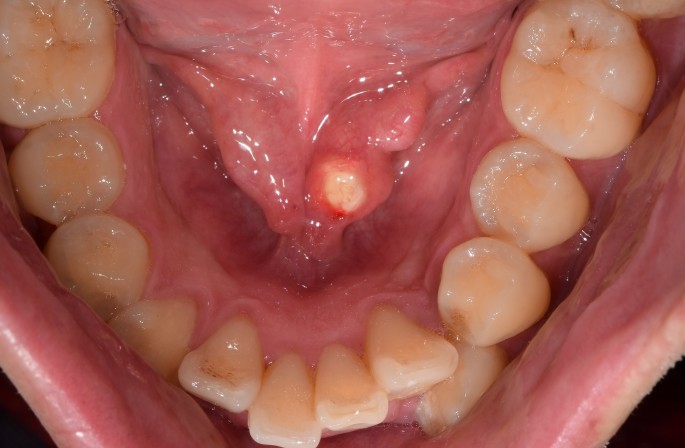

타석증은 침샘에 돌이 생기는 질환입니다. 침샘은 입안을 촉촉하게 유지하고, 음식을 소화하는 데 필요한 침을 분비하는 기관입니다. 타석증은 침샘의 어느 부위에나 돌이 생길 수 있지만, 가장 흔하게 이하선에서 가장 잘 발생합니다. 출처 : 밥먹을 때 침샘이 부어올라요 :: 침이 배출되.. : 네이버블로그 (naver.com) 출처 : 침샘염에 좋은 음식 원인 종류 치료 타액선염 .. : 네이버블로그 (naver.com) 1. 타석증 원인 1) 침샘의 점도 증가 : 침이 끈적끈적해지면 돌이 생기기 쉽습니다. 2) 침샘의 배출 감소 : 침샘의 배출이 감소하면 침이 뭉쳐져 돌이 생기기 쉽습니다. 3) 침샘관의 염증과 칼슘염 침착 : 침샘관의 염증과 칼슘염 침착으로 인해 돌이 생길 수 있습니다. 2. 증상 1) 침..